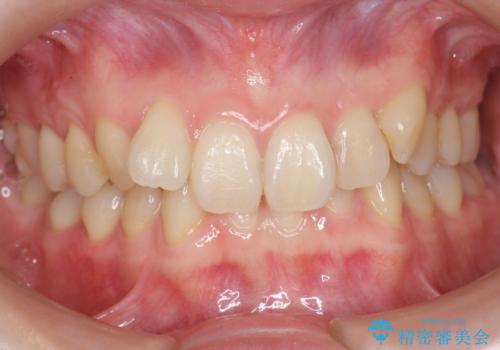

前歯のがたつき、八重歯 インビザラインで抜歯矯正

- 前歯のがたつきを主訴に来院。

下の前歯は生まれつき1本少ない状態でした。

左上の犬歯が入りきらずねじれており、かみ合わせもずれていました。

左上の小臼歯を1本抜いて治療しています。

前歯は内側に傾いており(ラビッティング)、過蓋咬合(深いかみ合わせ)を呈していました。

難しい治療でしたが綺麗に咬み合わせることができ、また前歯もしっかり当たるように治療できました。